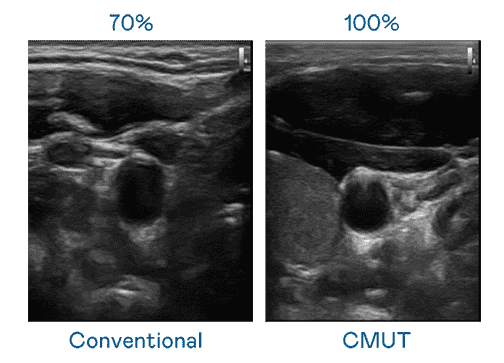

CMUT 技术是一种用电容式微机电元件来产生超音波讯号的技术。。与传统 PZT 压电式技术相比,,CMUT 频宽增加 30%,,,,更宽频的超音波讯号让影像解析度大幅提升,,是实现高影像品质医疗超音波扫描、、、、促进精准医疗发展的关键技术。。。。

大频宽带来超清晰影像

超音波影像的解析度高低,,首先取决于探头能发出的讯号频宽。。。彩霸王 CMUT 可提供高清晰的超音波讯号,,,,提供高频宽、、高灵敏度、、、影像纹理细节更高的超音波影像,,,协助医护人员缩短影像判读时间及利用精准的医疗影像进行诊断。。